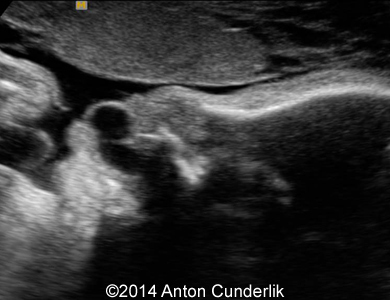

Image 1: 21 weeks of gestation. Normal fetal profile, no anomalies were found during the scan.

Image 2, 3, 4, 5, 6, 7: 30 weeks of gestation; the images show cystic structure within the fetal tongue that later turned out to be thyroglossal cyst.